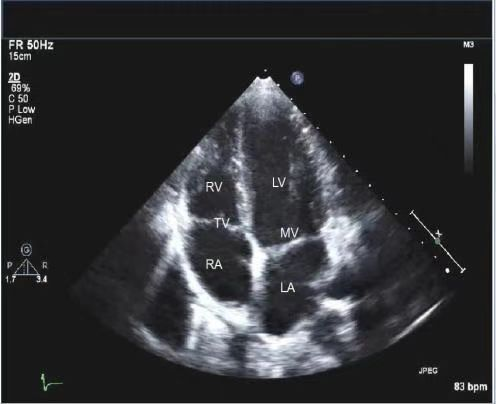

心脏彩色多普勒超声检查是一种实时、动态的心脏超声检查技术,没有放射性和毒性,是一种安全、无创、可重复性高的超声检查技术。心脏超声有两种检查方式:经胸超声和经食道超声。